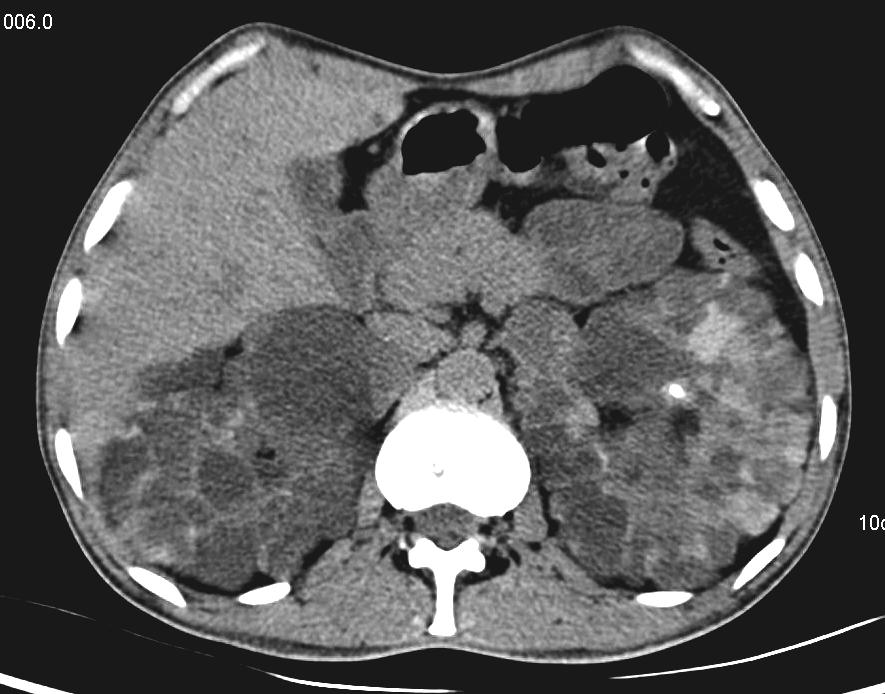

CT scan axial section at the level of kidneys showing enlarged bilateral kidney and they are replaced by multiple cystic lesions of variable sizes. Features consistent with Austosomal dominant polycystic kidney disease.